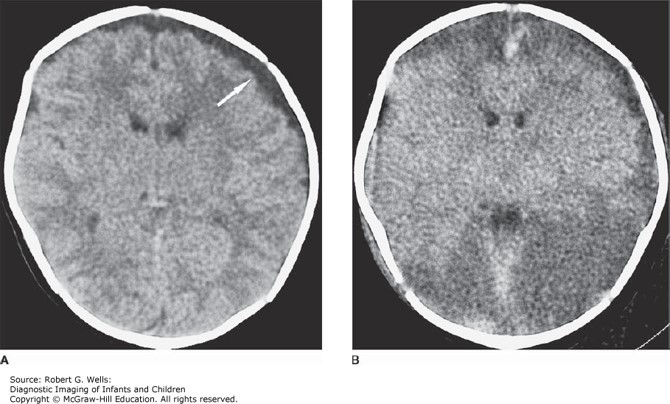

A 10-day-old male infant is admitted to the pediatric intensive care unit (PICU) for fever, seizures, and somnolence.

His anterior fontanelle is full. A CT scan of the head did not show acute abnormalities. CSF showed elevated white blood cells with mostly neutrophils, elevated protein, and low glucose. You suspect meningitis and start antibiotics.

The correct answer is “C.” It is important to know the common organisms causing acute bacterial meningitis in each age group. (See Table 23–2.) The most common causes of meningitis in a newborn are group B StreptococcusE. coli, and Listeria. The typical empiric antibiotic regimen for neonatal meningitis is ampicillin and cefotaxime or gentamycin. Listeria is resistant to cephalosporins, which is why you need to include ampicillin. Group B Streptococcus is sensitive to penicillins. E. coli is a gram-negative rod, and is covered by cefotaxime and gentamycin.

Photo: Wells RG. Diagnostic Imaging of Infants and Children; 2015